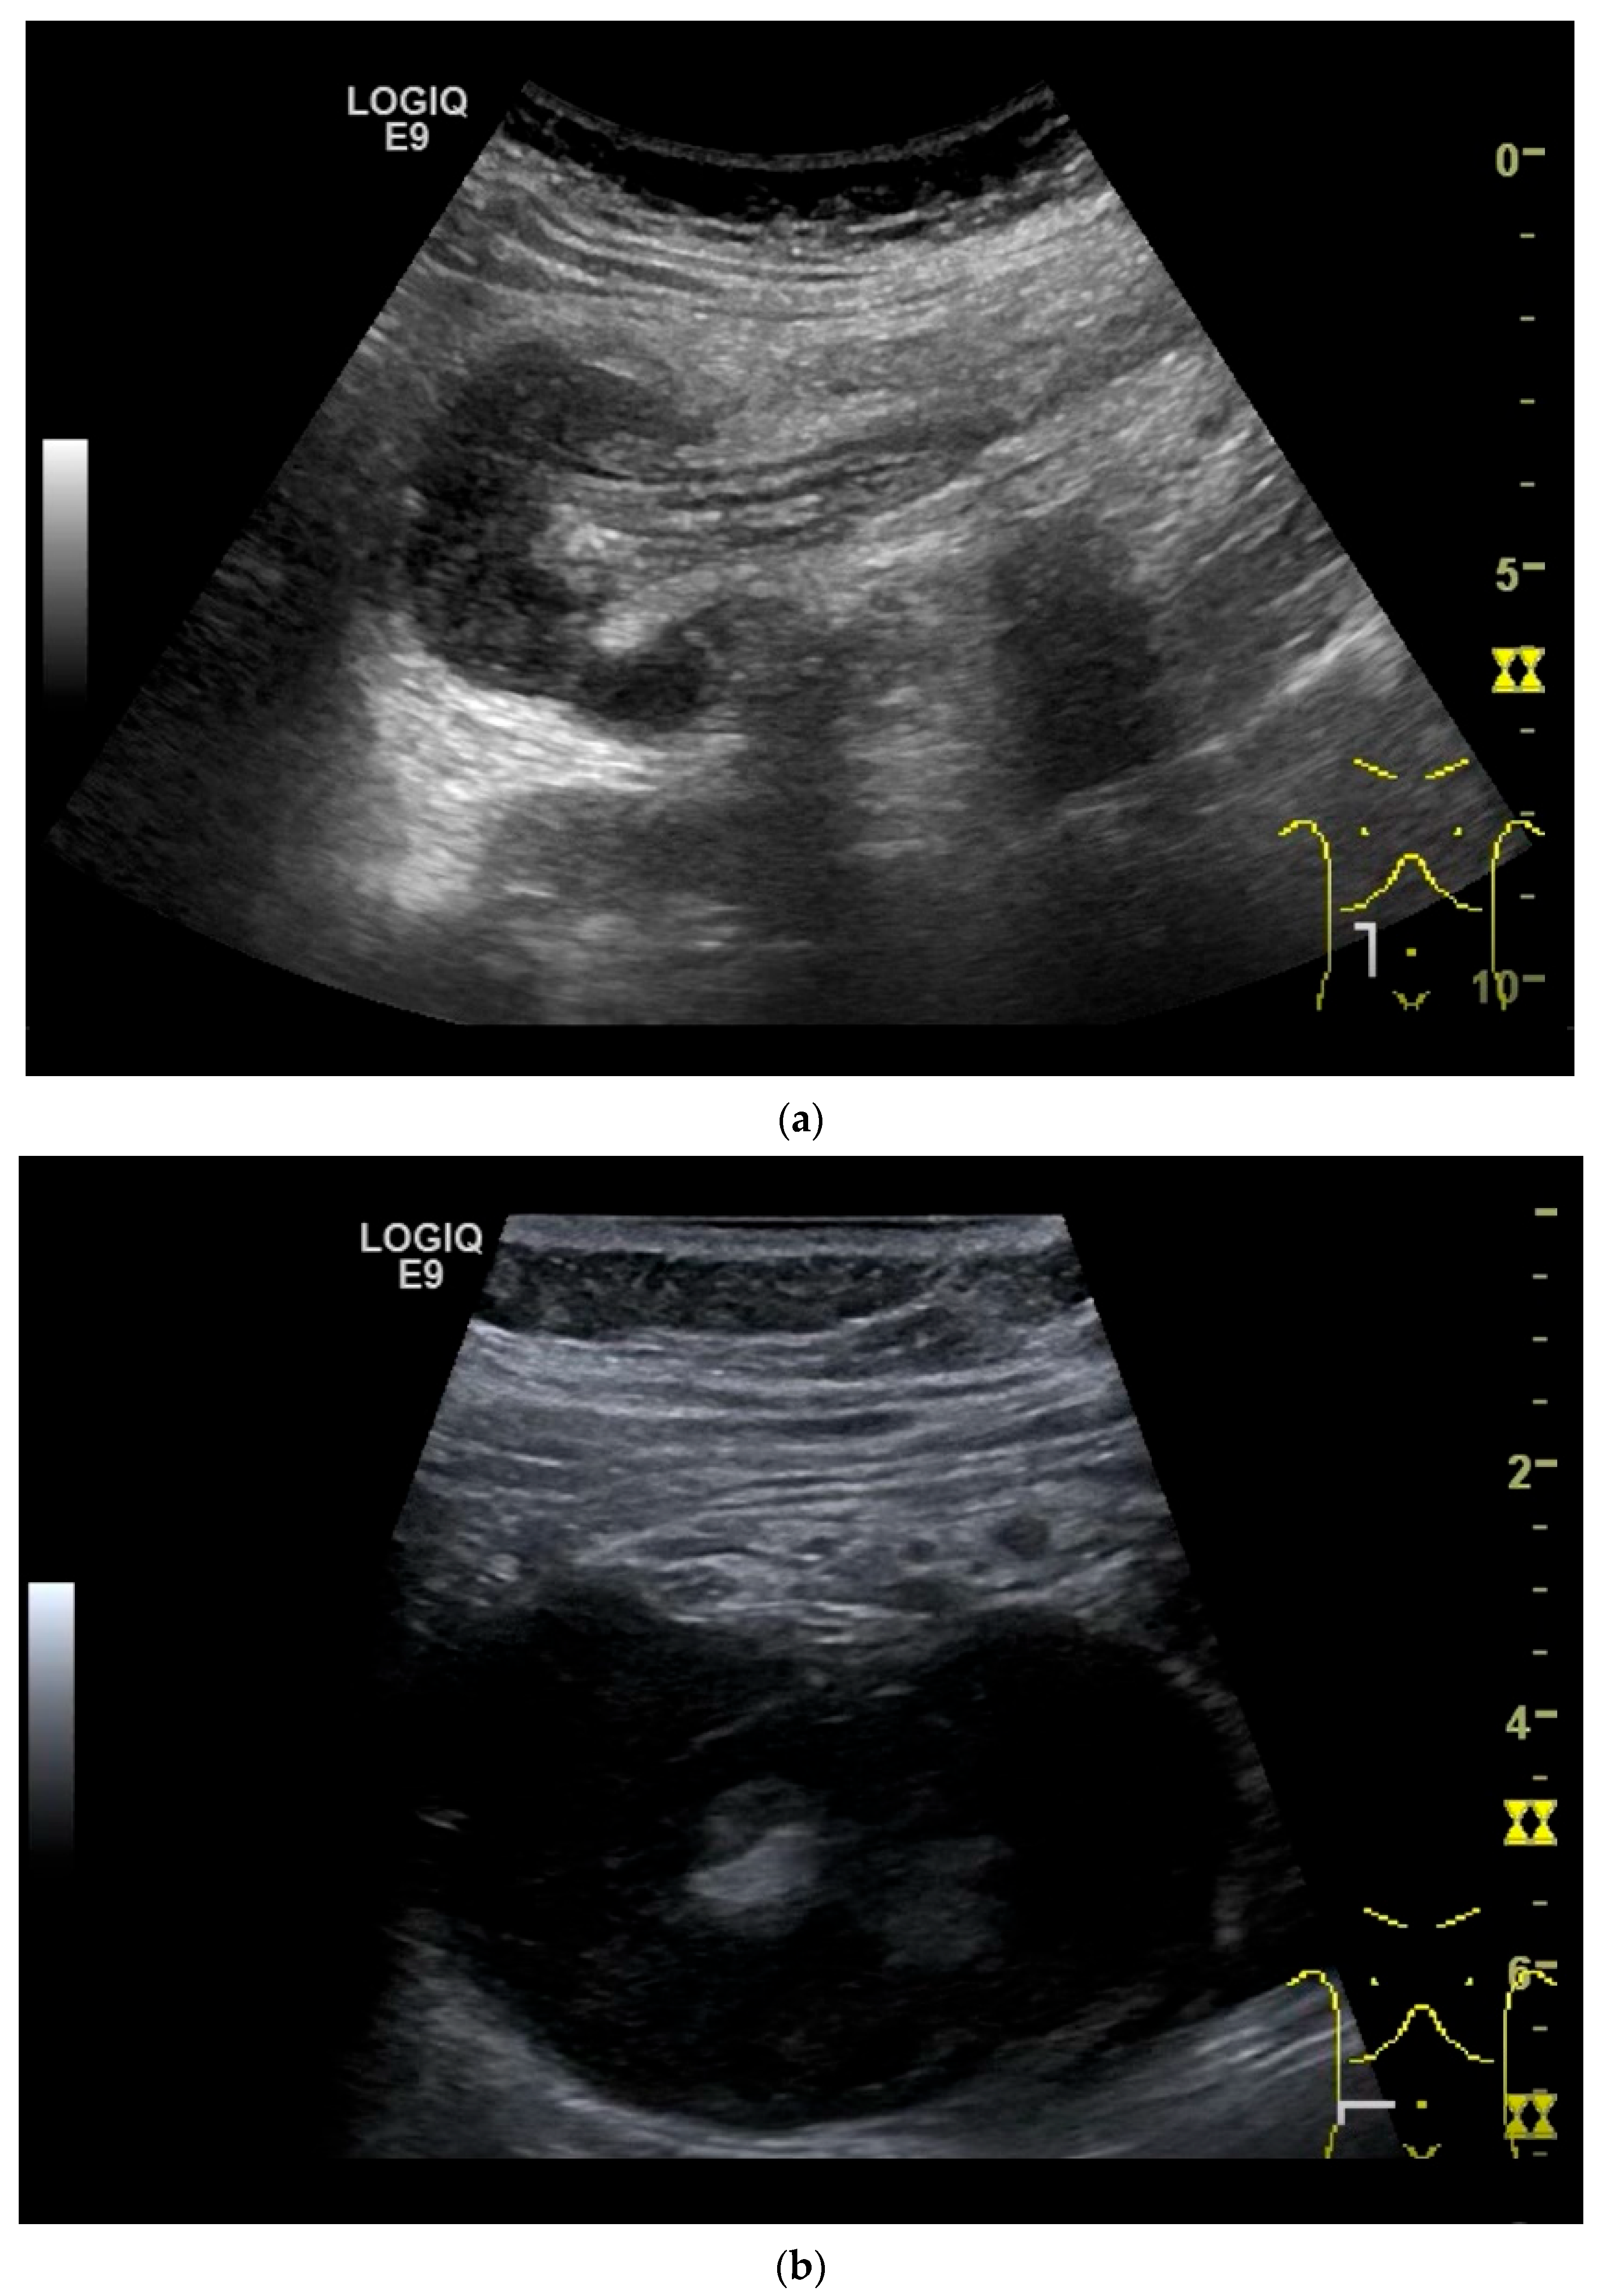

Figure 10.

Diffuse large B-cell lymphoma (DLBCL). In the right mid-lower abdomen, a large, smoothly circumscribed mass is present around the ileum (“pseudo kidney sign” (a)). Using a high-resolution linear transducer, the mass appears smoothly circumscribed and almost anechoic (b). The ileum runs centrally, and the echogenic wall is clearly defined (c). This wall does not merge into the mass. Since the mass is almost anechoic, it is also difficult in different transducer positions to distinguish whether it is a liquid lesion or a solid mass (b,c). CEUS with 2.4 mL SonoVue (9 MHz linear transducer) shows homogeneous arterial enhancement (d), but the intensity decreases with time in the venous phase (e). The ileal wall enhancement centrally within the mass is more intense than that of the tumor (d,e).